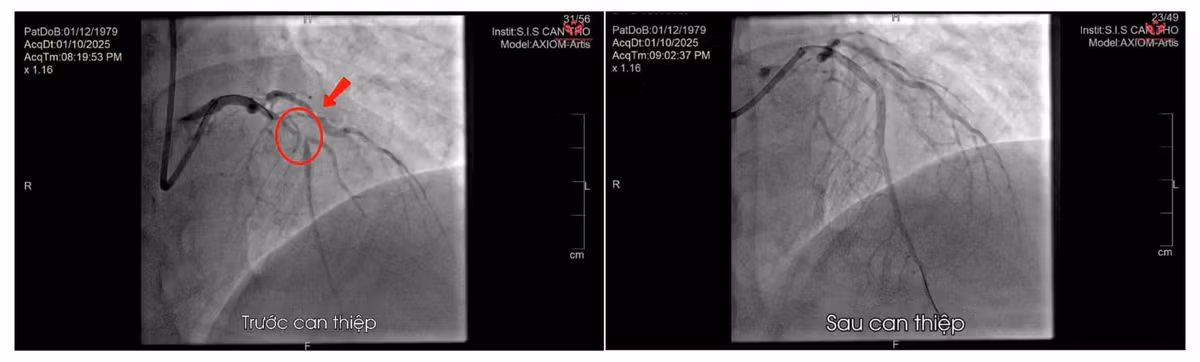

Kết quả chụp mạch vành cấp cứu ghi nhận tắc đoạn gần nhánh liên thất trước. Hình ảnh trước – sau can thiệp - Ảnh BVCC

Ê-kíp tim mạch khẩn trương hội chẩn và chỉ định chụp mạch vành cấp cứu, phát hiện tổn thương hẹp rất nặng ở đoạn gần nhánh liên thất trước. Bệnh nhân được đặt stent mạch vành cấp cứu để tái thông dòng máu.